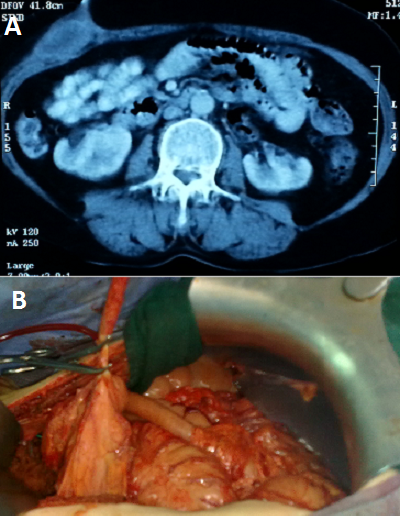

La fistule appendiculo-cutanée est une communication anormale entre le tube digestif et la peau à travers l'appendice. Elle représente une complication rare de la perforation appendiculaire au cours de l'appendicite et une urgence chirurgicale. Nous rapportons le cas d'un patient âgé de 48 ans, admis aux urgences pour des douleurs fébriles de la fosse iliaque droite, avec issu de pus à travers un orifice situé au niveau du flanc droit. L'examen clinique avait mis en évidence un orifice de 0,5 cm de diamètre situé au niveau du flanc droit donnant issu à de pus verdâtre, avec une défense de la fosse iliaque, chez un patient fébril à 38,2C. Le bilan biologique avait montré une hyperleucocytose à 15000/mm3, avec une CRP à 65 mg/l. Une échographie abdominale a été en faveur d'une appendicite aigue avec un abcès pariétal en regard. Le scanner abdomino-pelvien avait révélé un aspect d'appendicite aigue compliquée d'une fistule appendiculo-cutanée et d'un abcès pariétal en regard (A). Le patient a été opéré par laparotomie médiane avec découverte d'une appendicite aiguë suppurée avec un appendice de 7 cm de long, fistulisé à la peau au niveau du flanc droit, siège d'un abcès pariétal d'environ 20 cc de pus prélevé (B). Le geste a consisté à une appendicectomie rétrograde après déconnexion de la fistule et un drainage de l'abcès. Les suites post opératoires ont été simples et le patient est sorti de l'hôpital à j+4. L'examen anatomo-pathologique de la pièce opératoire est revenu en faveur d'une appendicite aiguë suppurée sans signes de malignité.